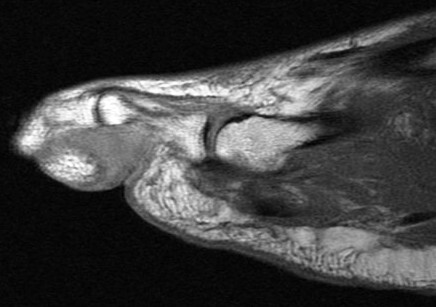

75 y/o male with toe mass.

Proven. Non painful. Mass of the skin at the base of the fourth toe. Patient sought medical attention due to the presence of the mass rather than symptoms. Last hidden image is enhanced. The disorder is rare. Reference article.

Nodular Localized Cutaneous Amyloidosis